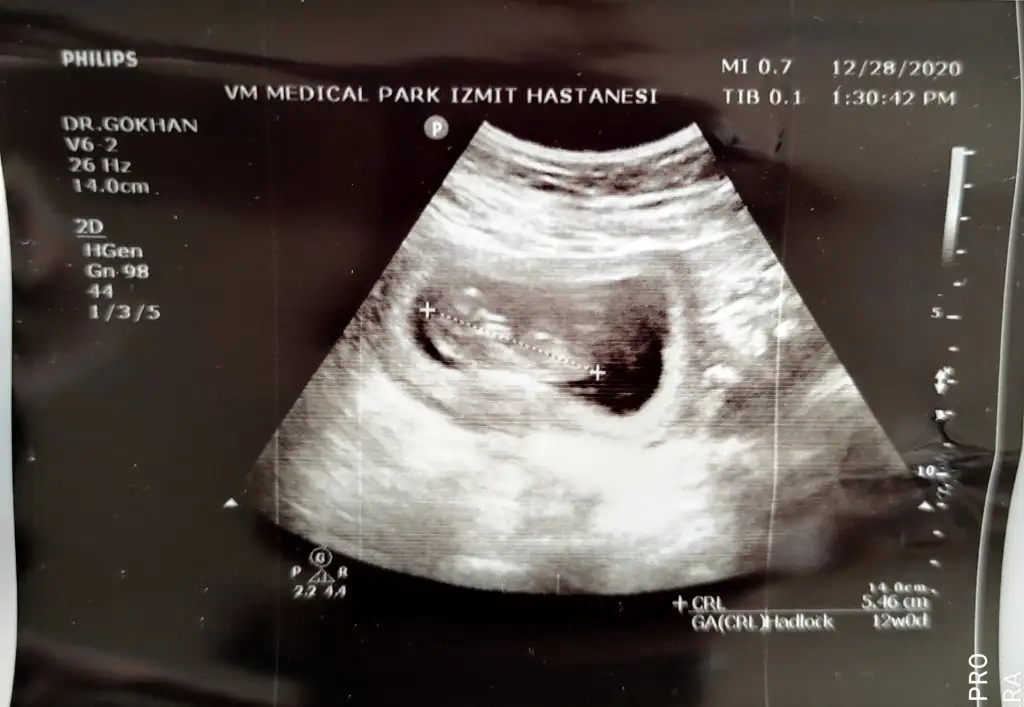

Ikra meyra merhaba Banada bakarmısınız lütfen 2 hafta önce de yazmıştım doktor a gittim bugün

• IMG_20201228_170721.webp

24,2 KB · Görüntüleme: 51

• IMG_20201228_170707.webp

32 KB · Görüntüleme: 50

• IMG_20201228_170650.webp

19,6 KB · Görüntüleme: 67